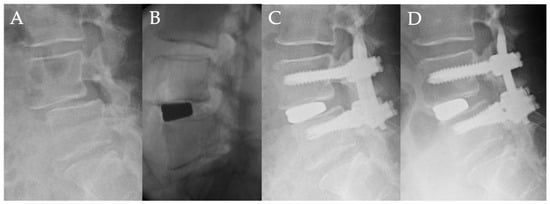

Fifty-four-year-old woman with lumbar degenerative spondylolisthesis (L4/5) (Figure 3).

From four years ago, she had bilateral sciatica that gradually worsened, and the intermittent claudication was reduced to 3 min. The patient was referred to our hospital. The chief complaint was low back pain and bilateral sciatica at her initial visit, and there was no obvious muscle weakness. The preoperative JOA score was 14 points. Lateral radiograph showed L4 anterolisthesis of Grade 2 (slip ratio of 25%), and magnetic resonance imaging showed severe stenosis at L4/5. Indirect decompression surgery, using lateral interbody fusion and percutaneous pedicle screw was performed. The slippage of L4/5 was corrected from 25% preoperatively to 16% after lateral interbody fusion, and that was reduced to 3% after a percutaneous pedicle screw procedure. One year after surgery, the slippage was 3%. The correction rate of slippage was 36% by lateral interbody fusion and 52% by percutaneous pedicle screw, and the total correction rate was 88%. There was no loss of correction one year after surgery. The final JOA score was 27 points, and there was no neurological complication.

Figure 3. Fifty-four-year-old woman with lumbar degenerative spondylolisthesis: (A) Preoperative lateral radiograph showing L4-L5 spondylolisthesis with 25% vertebra slippage. (B) Intraoperative fluoroscopic view showed that the slippage of L4/5 was corrected to 16% after lateral interbody fusion. (C) Postoperative lateral radiograph showed the slippage of L4/5 was corrected to 3% after percutaneous pedicle screw procedure. (D) Lateral radiograph one year after surgery showed no correction loss of slippage.